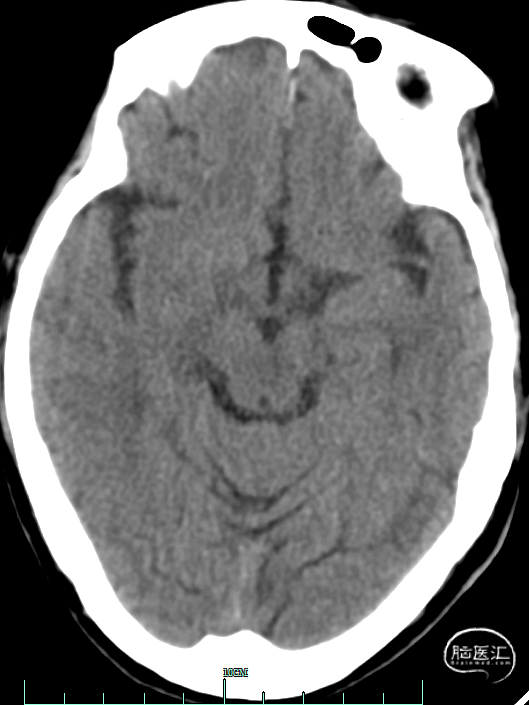

术前影像资料